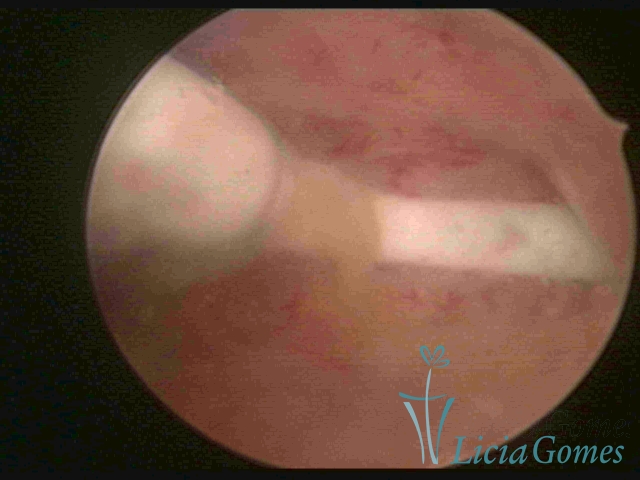

Cavidade uterina com DIU e muco claro acumulado